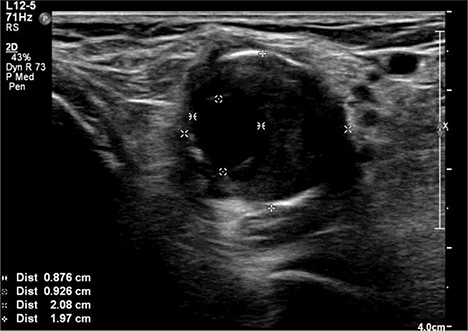

A 92-year-old female, independent from home, presented after multiple falls due to a four-month history of left foot drop. The foot drop had gradually worsened to the point that there was complete paralysis of ankle dorsiflexion and was associated with significant oedema of the foot. On examination, there was a large pulsatile mass in the popliteal fossa bilaterally. All peripheral pulses were palpable without any signs of ischemia. The most striking examination finding was complete paralysis of left ankle dorsiflexion with 0 out of 5 power. Ultrasound revealed that there were (Fig 1) bilateral popliteal artery aneurysms, which was larger on the left, causing displacement and impingement of the common peroneal nerve at the knee crease (Fig 2). Further computed tomography angiogram demonstrated an unruptured left PAA measuring 22 × 21 mm in maximal dimension over a distance of 24 mm (Fig 3). Intraluminal thrombus was also noted with 60% luminal stenosis. Distally, the arteries were heavily calcified with two-vessel runoff at the ankle. An emergency endovascular repair of the left PAA was performed by using 8 mm × 15 cm and 7 mm × 10 cm Gore Viabahn stents (Fig 4). The stents were deployed after a balloon-angioplasty and adequate decompression of the aneurysm was achieved. The postoperative period was uneventful, and patient’s pre-existing aspirin was continued. The leg and foot oedema improved rapidly over the subsequent few days. At follow-up in 12 weeks, the patient showed some return of motor function of the ankle and was walking with ankle splint. Her left leg remained well perfused with palpable pulses.

Ultrasound image of left popliteal artery aneurysm, causing displacement and impingement of the common peroneal nerve (indicated by the white arrow).